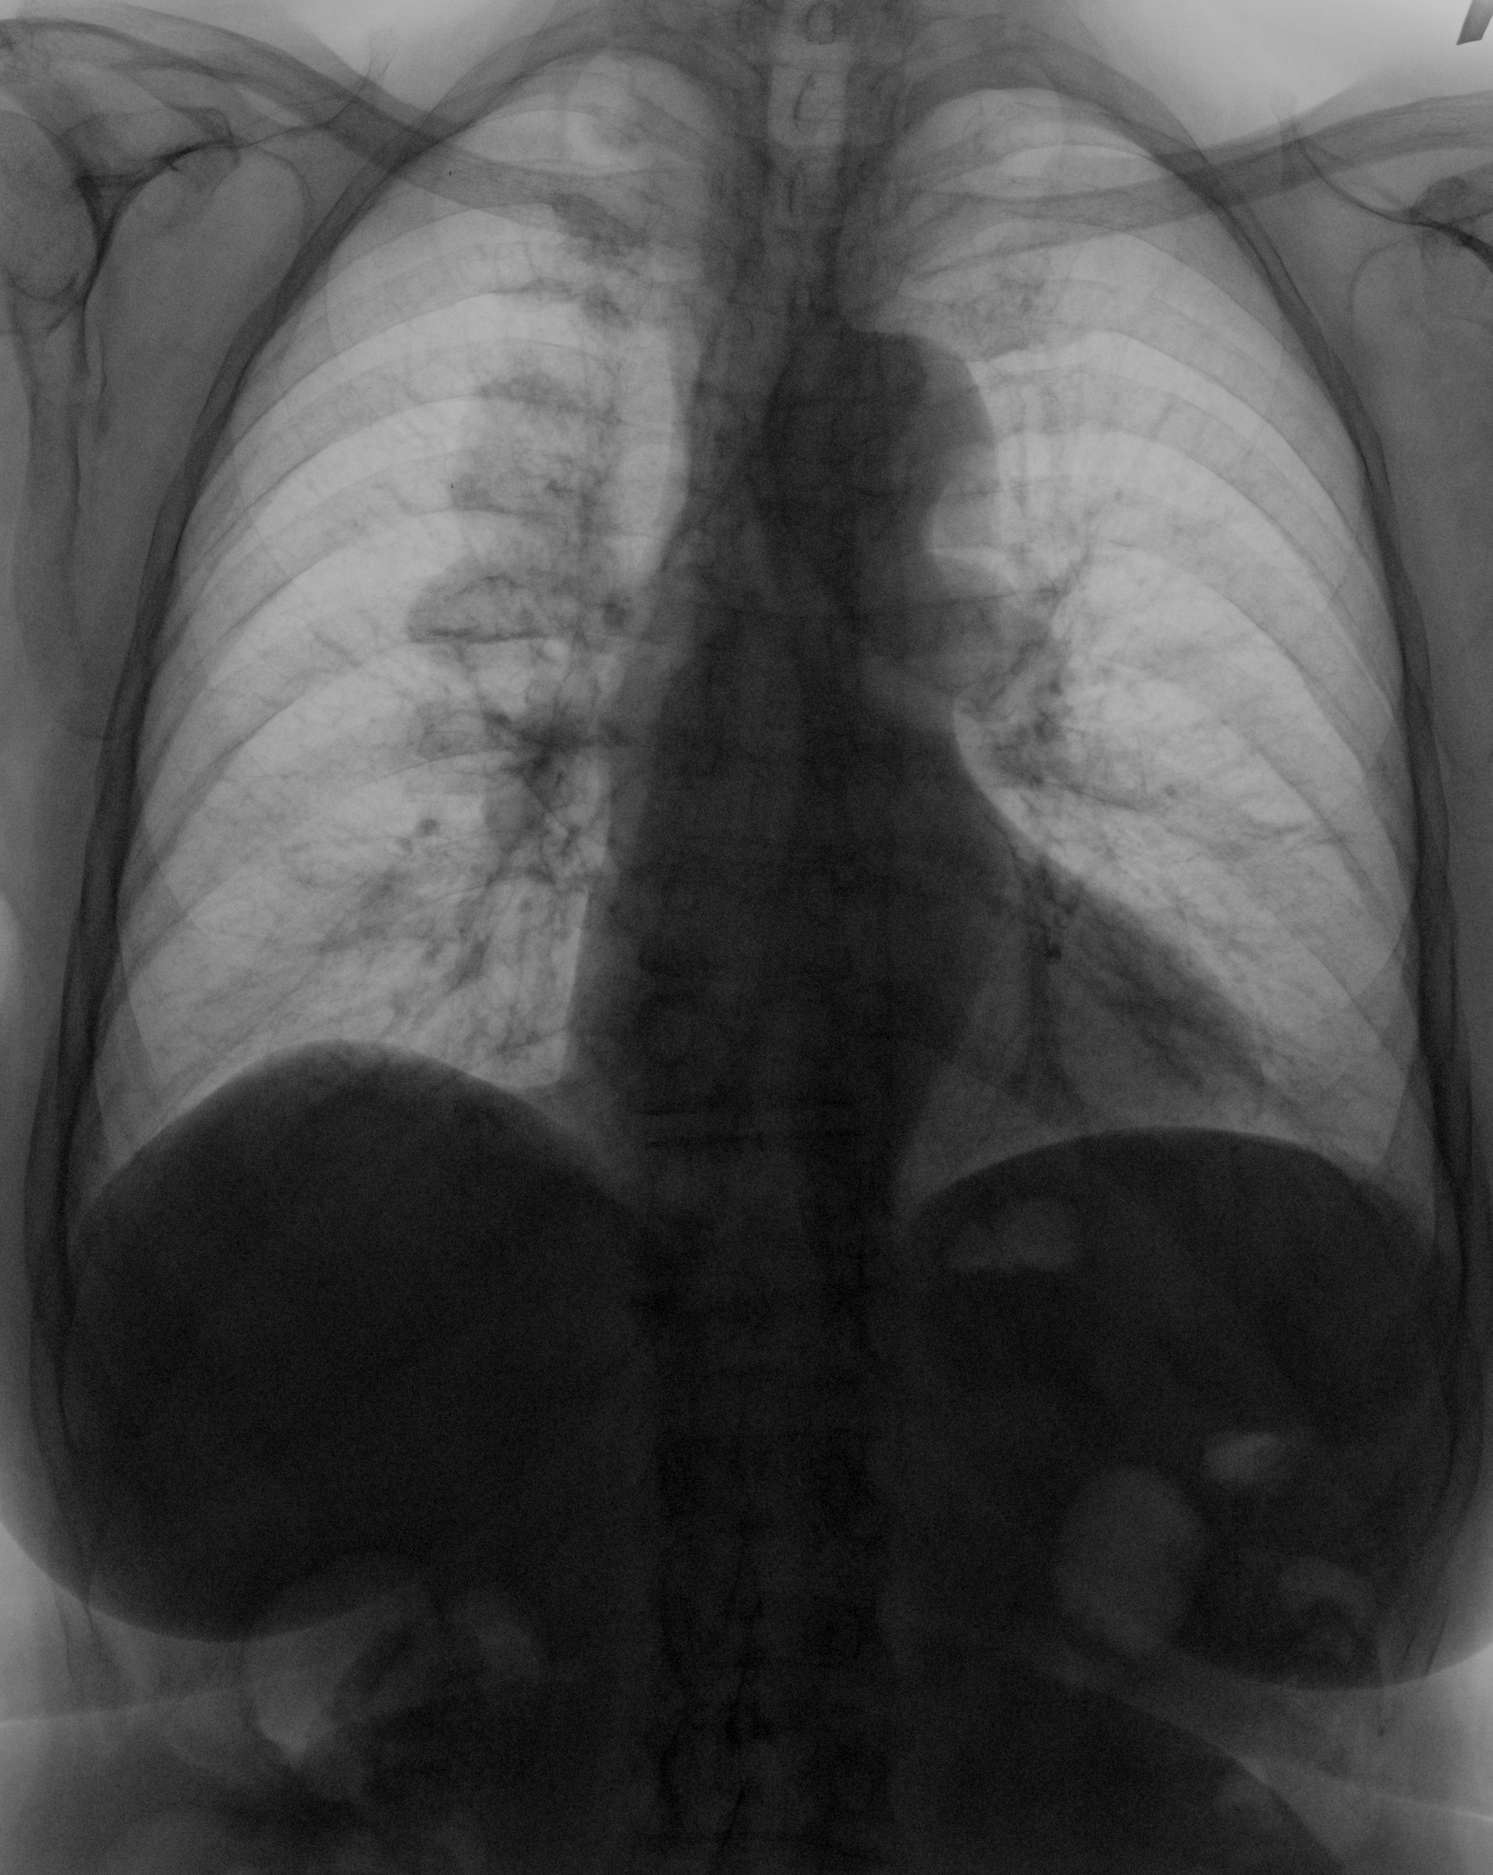

20.11.2010 Рентгенография органов грудной полости.

Пациентка 82 года поступила в приемное отделение  с Ds: ЖКБ. К нам направили для исключения пневмонии и на предмет свободного газа в брюшной полости.

Имеется обызвествление по задней поверхности костальной плевры справа.

Интенсивность для обызвествления мала. Возможен и острый процесс.

На 100% выпот не исключил бы, но пестрота картины против острого процесса.

Снижение высоты+ клиновидная деформация 12 грудного  позвонка.

.+ за осумкованный выпот.

На все 100%.

Может что-то застарелое, типа "древних ретенционных кист"?

+1 (поддержу всё). Если не зло, то выпот. УЗИсты "допилят"!